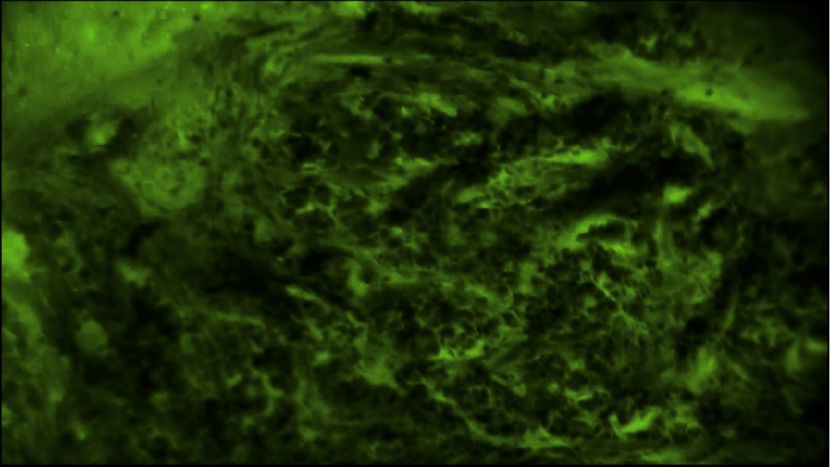

術(shù)中EndoSCell?細(xì)胞圖像如下:

間質(zhì)組織:少量煙霧狀焦痂細(xì)胞,細(xì)胞核大小均一、形態(tài)正常,密度低,未見(jiàn)腫瘤細(xì)胞

EndoSCell?鏡下常見(jiàn)的乳腺浸潤(rùn)性癌腫瘤細(xì)胞圖像:細(xì)胞核大大小小且密度很高